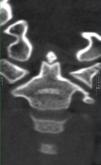

Se describe el caso de un varón de 7 años que es trasladado a Urgencias de Pediatría (UPED) con bajo nivel de consciencia tras traumatismo craneoencefálico secundario a caída en bicicleta. La familia refiere traumatismo frontal contra un bordillo, sufriendo una pérdida de consciencia inicial de unos 10 s de duración. A su llega a UPED, se constata tendencia al sueño, con Glasgow 14/15. Se realiza inmovilización cervical con collarín rígido y TC cráneo-cervical en la que se observa la persistencia de parte de la sincondrosis de la odontoides y un pequeño fragmento óseo en el extremo distal de la misma, no fusionado al resto, de 7mm de diámetro (figs. 1–3). Este se corresponde con un osículo de Bergmann (ossiculum terminale de Bergmann) y no debe confundirse con el os odontoideum (falta de fusión entre la apófisis odontoides y el cuerpo del axis) ni con una fractura de odontoides1. Dicho osículo es un hallazgo normal durante el proceso de osificación de la odontoides, tratándose de un centro de osificación secundario, que aparece en torno a los 3-6 años, fusionándose en torno a los 12 años de edad. No precisa tratamiento alguno, ya que es estable y raramente da síntomas2. Nuestro paciente evolucionó favorablemente, siendo alta tras 24 h de observación, recomendándose seguimiento posterior en la consulta de Traumatología.